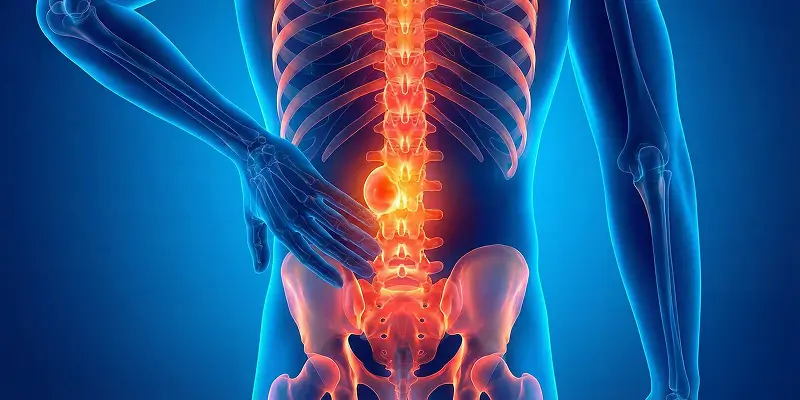

Patolojik kırık, kemiğin altta yatan hastalık nedeniyle zayıflaması sonucu hafif darbelerle oluşan kırık türüdür. Nedenleri, belirtileri, teşhisi ve tedavisi hakkında bilgi.

Kemik enfarktı, kemiğe giden kan akışının bozulması sonucu kemik dokusunun canlılığını kaybetmesidir. Nedenleri, belirtileri, tanı ve tedavi yöntemleri.

Gençlerde ve omurgada görülen, ağrılı seyreden Osteoblastoma'nın tanısı ve cerrahi temizlenme süreci.